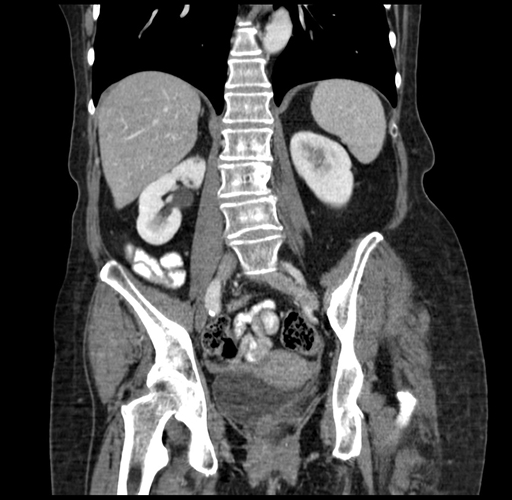

Pre-Chemo: Coronal Venous

Coronal Venous